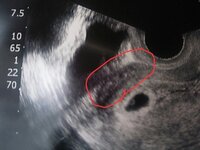

Yahoo!知恵袋妊娠7週5日。

胎のう、卵黄嚢のみ確認。胎芽未確認。

流産の可能性は高いでしょうか?